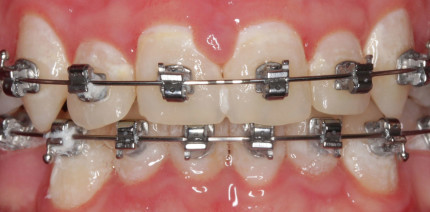

Die vollständig individualisierte linguale Apparatur (VILA) hat sich als qualitätsorientierte und effiziente Behandlungsmethode in der modernen...

Die vollständig individualisierte linguale Apparatur (VILA) hat sich als qualitätsorientierte...